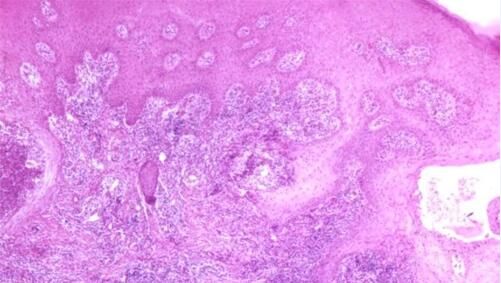

艾滋病感染性皮肤损害—单纯疱疹:较一般患者严重,复发频繁,皮损分布呈局限性或播散性。表现为持续性口腔、生殖器、肛周重度疱疹,发生于肛周者可反复发作.长期不愈,伴深溃疡。